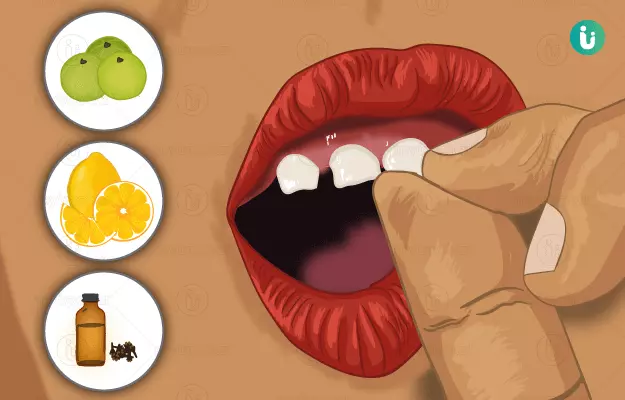

क्या है? दाँतों का हिलना

दाँतों का हिलना एक ऐसी स्थिति है जिसमें दाँत अपने सामान्य स्थान से हिलने लगते हैं। यह स्थिति किसी भी उम्र के व्यक्ति को प्रभावित कर सकती है, लेकिन यह बच्चों और युवा वयस्कों में अधिक आम है। दाँतों का हिलना कई कारणों से हो सकता है, जिनमें शामिल हैं:

दाँत हिलने के कई कारण हो सकते हैं-

(1) दाँतों के पट्ठों की शिथिलता

(2) पायेरिया

(3) चोट आदि ।

(4) कई बार यह रोग पारा (Mercury) के विषैले प्रभाव के कारण भी हो सकता है l